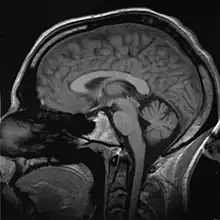

Biomechanics

.jpg)

Biomechanics is the study of the structure and function of the mechanical aspects of biological systems, at any level from whole organisms to organs, cells and cell organelles,[4] using the methods of mechanics.[5]